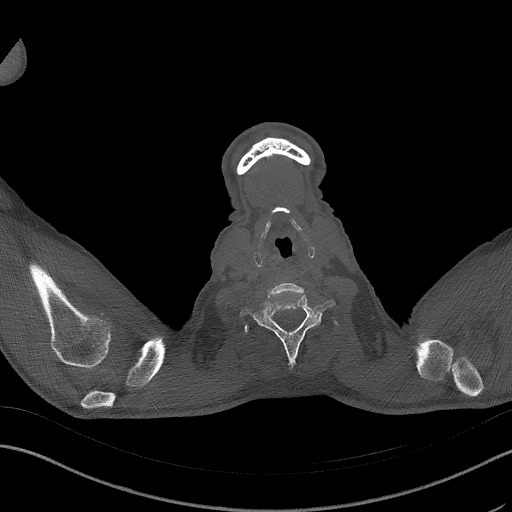

Three tasks have been used to evaluate the performance of our approach. First, for BM segmentation, we utilized the BM-Seg dataset Afnouch et al. (2023). This dataset comprises data from 23 CT scans of 23 patients diagnosed with bone metastasis. A total of 1517 slices were confirmed to exhibit bone metastasis infections by three expert radiologists and were labeled for bone metastasis and bone regions masks. We followed the same splits as described in Afnouch et al. (2023), where five-fold cross-validation evaluation scenario were introduced.

For the BM segmentation task, we compared the predicted masks generated by our approach with those from three competitive methods (Figure 5), which had proven to be the top performers, as shown in Table 3. These competitors include MISSFormer Huang et al. (2022), UCTransNet Wang et al. (2022a), and EDAUnet++ Afnouch et al. (2023). In the first two examples, we examined cases where Bone Metastasis had infected all bone regions within the slice. A closer inspection of the predicted masks revealed that most approaches were successful in highlighting the infected regions. However, it was evident that MISSFormer and EDAUnet++ struggled to capture segmentation details accurately. In contrast, our approach and UCTransNet excelled in matching the details present in the ground-truth masks. The remaining three examples represented slices where only a portion of the bone was infected by BM, which is a particularly challenging aspect of BM segmentation. In the third example, the comparison methods incorrectly segmented a part of the bone as a Bone Metastasis lesion. In contrast, our approach accurately matched the ground-truth mask in these scenarios. The last two examples demonstrated our approach’s ability to capture intricate lesion details effectively, showcasing the efficiency of our proposed compound encoder, which integrates Transformer and CNN features. In summary, the visualizations and comparisons reaffirm the effectiveness of our approach in BM segmentation, particularly in challenging cases, and highlight its ability to capture intricate lesion details efficiently.

Slice Bone Mask MISSFormer UCTransNet EDAUnet+ D-TrAttUnet GT

Figure 5: Visual Comparison of Bone Metastasis Segmentation Models Trained with Different Architectures.